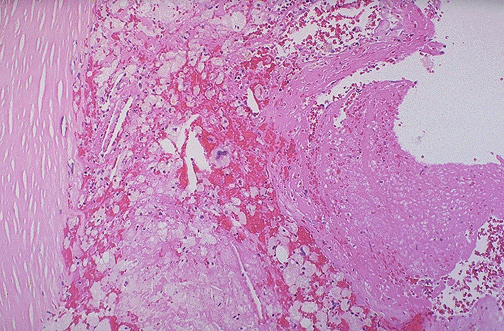

This is an atheromatous plaque in a coronary artery that shows endothelial denudation with disruption and overlying thrombus formation at the right. The arterial media is at the left.